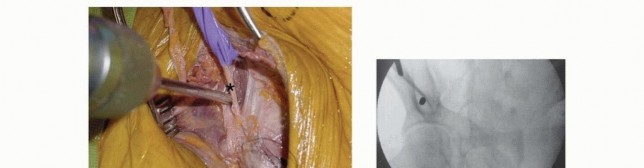

This requires that the drill be held more cephalad (directed caudad) than expected to allow proper position within the desired supra-acetabular bone (superior and cephalad to the acetabulum) rather than the thin bone of the ilium. Triple cannulated drill sleeves are used to protect soft tissues. The fixation pin is inserted, allowing the cortical walls of the ilium to establish direction. An image intensifier may aid in elective nonemergent fixator application. 2. ## Supra-acetabular Technique The patient is positioned supine on a radiolucent table. Safe introduction and proper positioning of the pin require the assistance of fluoroscopic guidance. The open approach for pin placement begins with a vertically oriented 5- to 10-cm incision, depending on patient body habitus and prereduction pelvic deformity. A smaller transverse incision has been described in addition to entirely percutaneous techniques of pin insertion. This vertical approach begins along the lateral border of the anterior superior iliac spine, extending distally and lateral to the AIIS. The interval between the sartorius and tensor fascia lata is identified ( TECH FIG 4A). Tissue planes are developed with blunt dissection and the anterior inferior spine is palpated. The lateral femoral cutaneous nerve is most commonly identified medial to the anterior iliac spine. Anatomic studies have demonstrated the lateral femoral cutaneous nerve to have a variable course, often within 10 mm of inserted pins. 6 With blunt dissection and the use of protective drill sleeves, the lateral femoral cutaneous nerve may be adequately protected. Supra-acetabular pins should be inserted no less than 2 cm proximal to the joint to avoid intra-articular penetration. Capsular extension of the hip may be up to 16 mm superiorly.

An obturator oblique view with slight cephalad angulation

(obturator outlet view) is first obtained. A metallic marker is positioned 2 cm proximal to the hip joint under fluoroscopic control ( TECH FIG 4B). The trocar assembly is positioned under fluoroscopic control superior to the hip joint. Only the outer cortex is drilled. A triple cannulated guide facilitates atraumatic drill and pin insertion. The drill, followed by the pin, is directed within the pelvis, avoiding intra-articular penetration of the hip joint.

Pin angulation is typically 20 degrees medial from the vertical axis and slightly cephalad. The drill is directed toward and superior to the sciatic notch (30 to 45 degrees in the sagittal plane). Fluoroscopic guidance (iliac oblique view with slight cephalad angulation) ensures proper pin trajectory and depth of insertion ( TECH FIG 4C,D).

TECH FIG 4 • Supra-acetabular pin insertion technique. A. The interval between the sartorius and the tensor fascia lata is established (lateral femoral cutaneous nerve protected [

asterisk

]). B. An obturator outlet view identifies the proper pin entry site. C,D. An iliac oblique view with cephalad angulation directs the advancing pin. E,F. The rollover view (obturator oblique inlet view) ensures pin placement within the inner and outer tables of the pelvis. Intercortical pin orientation within the tables of the pelvis is monitored on an obturator oblique inlet view (“rollover view”) ( TECH FIG 4E,F). A 5-mm diameter, 50-mm thread length pin is inserted to the depth of the threads. A second pin may be inserted proximal to the first, if desired. 3. ## Frame Application and Reduction No frame, regardless of complexity, restores sufficient definitive fixation to vertically unstable lesions. 22 Accordingly, simple constructs are preferred to permit patient mobilization, abdominal access, and performance of subsequent diagnostic and therapeutic procedures. Accurate pin placement within the curved iliac crest mandates a nonparallel converging pin pattern. Pin clamps with a straight configuration require that pins be prestressed to conform and accommodate such clamps ( TECH FIG 5A). Those with an independent ball joint design offer an attractive alternative (TECH FIG 5B). 319